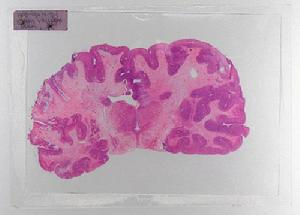

人腦冠部經過蘇木精和曙紅染色。每一張載玻片——連同載玻片載入器和條形碼閱讀器——都是改進型萊卡600B顯微鏡自動拍攝的。 8.冠部經過銀黃著色